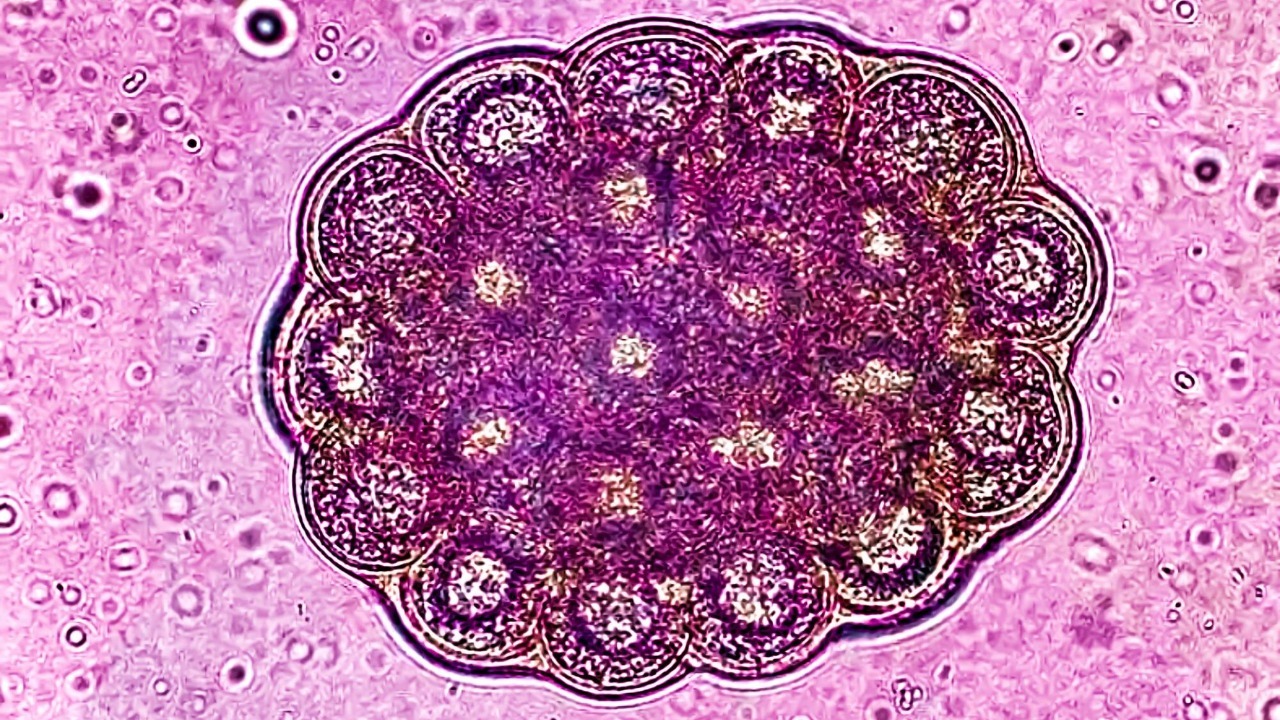

Cancer deaths surging worldwide, scientists warn of looming crisis

Read More: Cancer deaths surging worldwide, scientists warn of looming crisisCancer is tightening its grip on the world, with scientists warning that deaths are on track to soar within a…